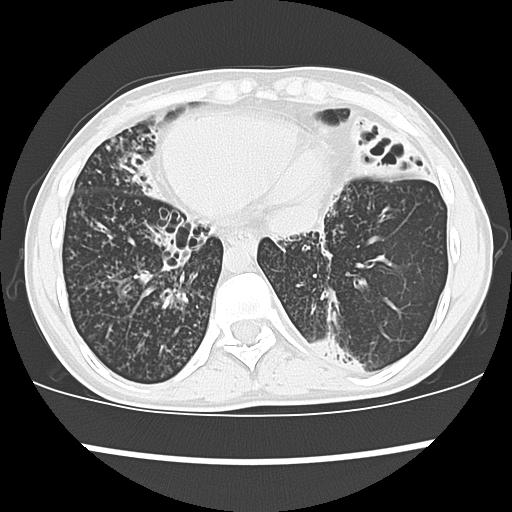

Синдром зиверта картагенера